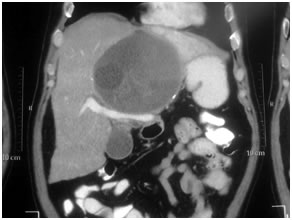

Haemangiomas:

Heamangiomas are benign lesions and generally warrant no therapy unless symptomatic. Lesions greater then 10cms are termed Giant haemangiomas and may cause symptoms like pain and organ compression leading to jaundice (bile duct) or vomiting (stomach). In such cases resection is required to relive the symptoms.